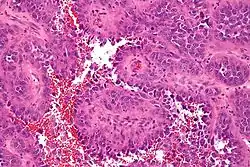

ساركومة وعائية[1] أو غرن وعائي[1] (بالإنجليزية: Angiosarcoma) هو سرطان في الخلايا التي تبطن جدران الأوعية الدموية أو الأوعية الليمفية. بطانة جدران الأوعية تسمى الطلائية المبطنة. من ناحية أخرى، يجب عدم الخلط بينها وبين الأورام الوعائية الكرزية.[2]

![]() صورة مجهرية للساركوما الوعائية (صبغة H&E). صورة مجهرية للساركوما الوعائية (صبغة H&E). | |